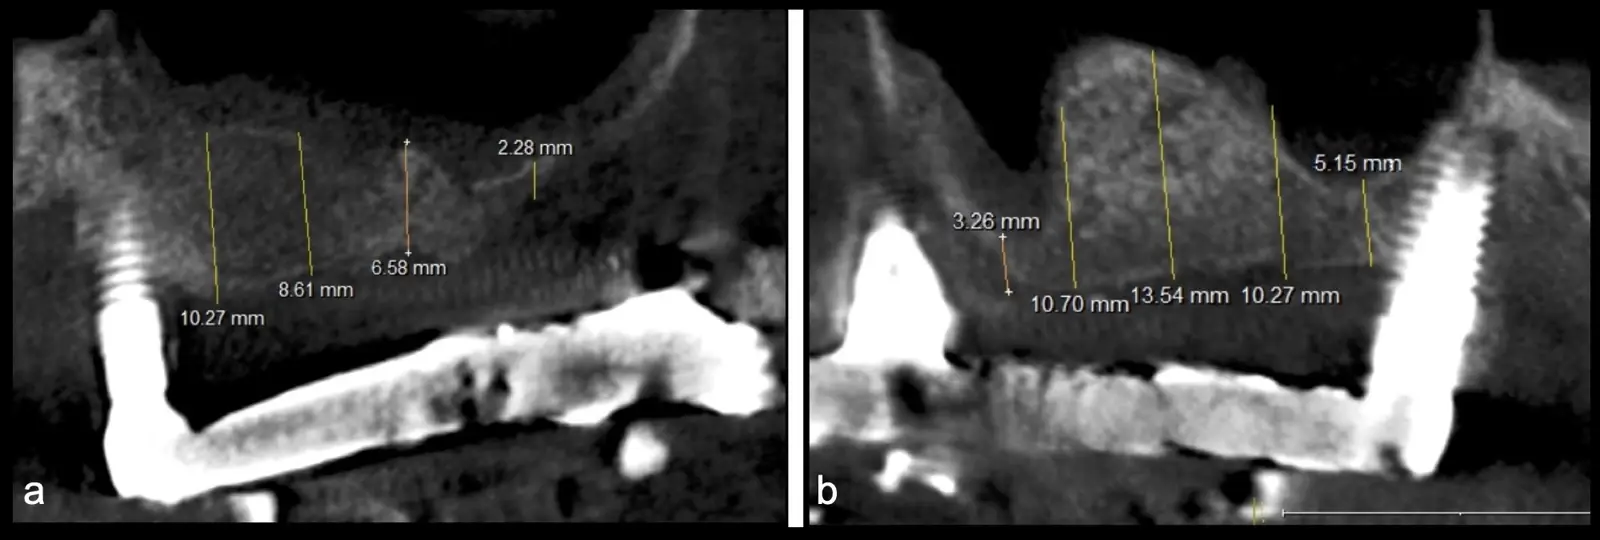

Figura 31. Control tomográfico post operatorio: corte sagital de ambos senos maxilares. (derecha e izquierda).